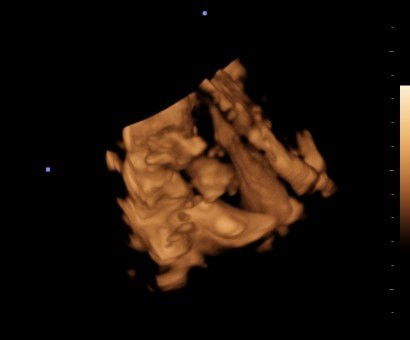

Usg 26 minggu

Usg 26 minggu.ini dedenya lg apa ya bun g jelas